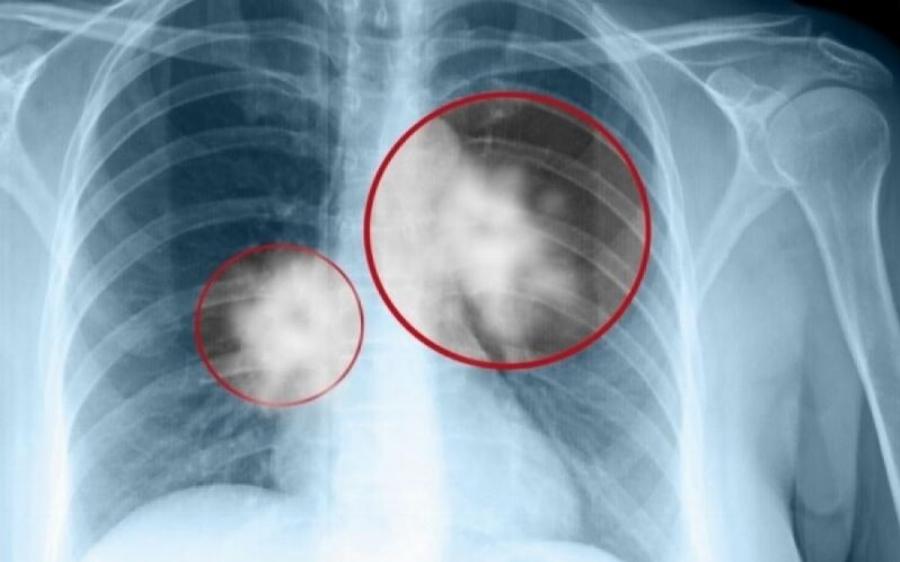

Καρκίνος του πνεύμονα: Πρόκειται για ένα συνηθισμένος και θανατηφόρο καρκίνο.

Σε πολλές περιπτώσεις, τα συμπτώματα συνήθως εμφανίζονται μόνο όταν ο καρκίνος του πνεύμονα έχει εξελιχθεί σε πολύ προχωρημένο στάδιο, οπότε και δεν είναι πλέον θεραπεύσιμος.

Όπως και πολλοί άλλοι καρκίνοι, ο καρκίνος του πνεύμονα μπορεί να ανιχνευθεί στο αρχικό στάδιο (στάδιο 1), οπότε είναι σημαντικό να αναγνωρίσουμε όλα τα συμπτώματα.